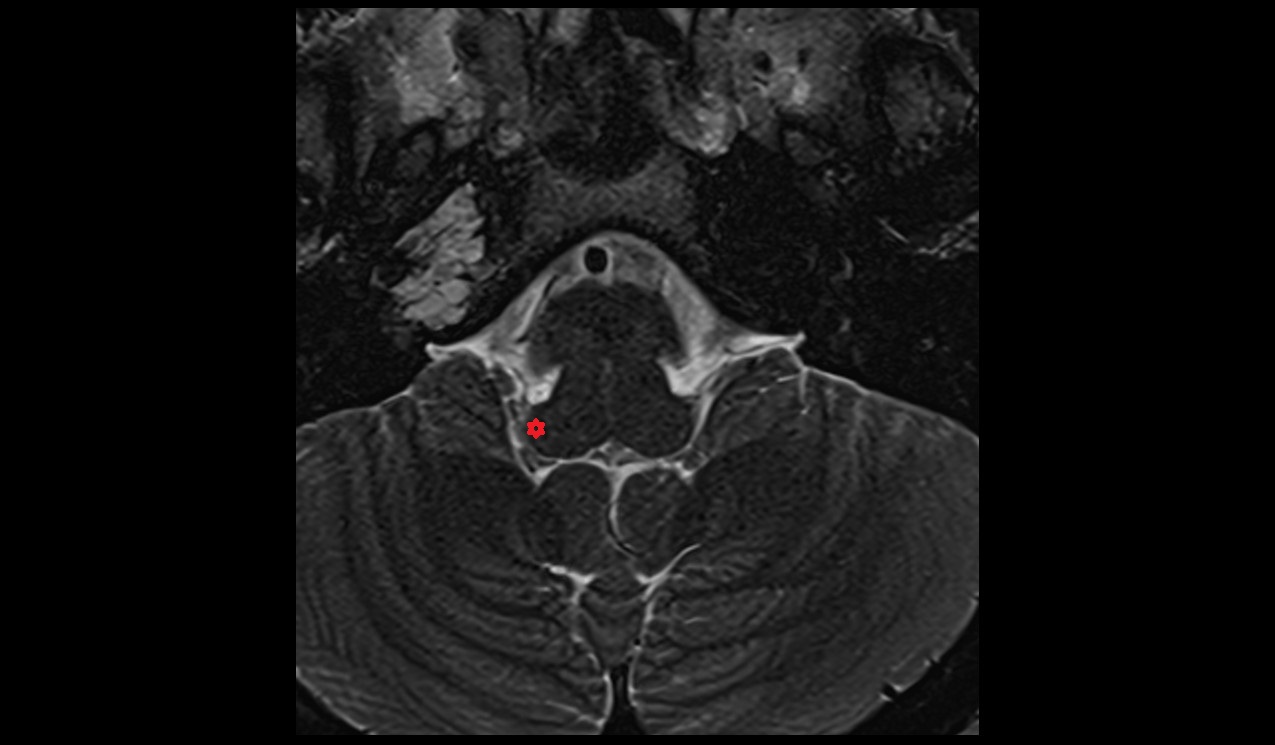

- Facet joint of vertebra (Zygapophyseal joints)